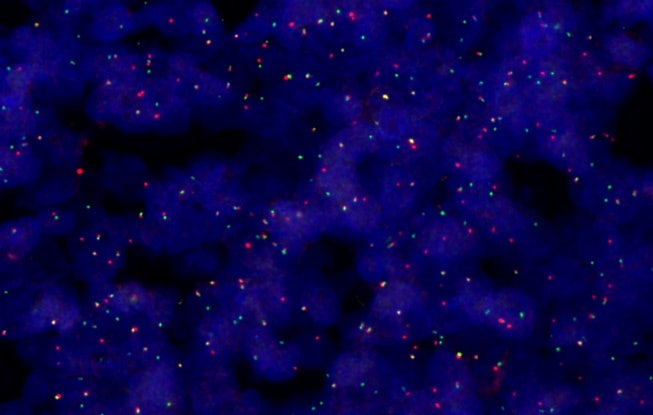

荧光原位杂交(FISH)分析,40X

SLIDEVIEW VS200系统最多支持六个高性能X Line物镜,采用真彩LED照明,配备色彩经过校正的相机配置文件,可提供清晰的全玻片图像。扫描仪经过精心设计,可稳定再现样品和染色特征,不仅大幅减少了重新扫描的需要,还支持高效诊断。

通过五种成像模式——明场、偏光、荧光、暗场和相衬——发现样品中的更多细节,还可在单次扫描中结合使用多种技术,进行更全面的观察。这种灵活性为观察组织学和细胞学样品提供了广泛的应用可能性,涵盖了从常规病理学到癌组织的复杂分子表征等应用。